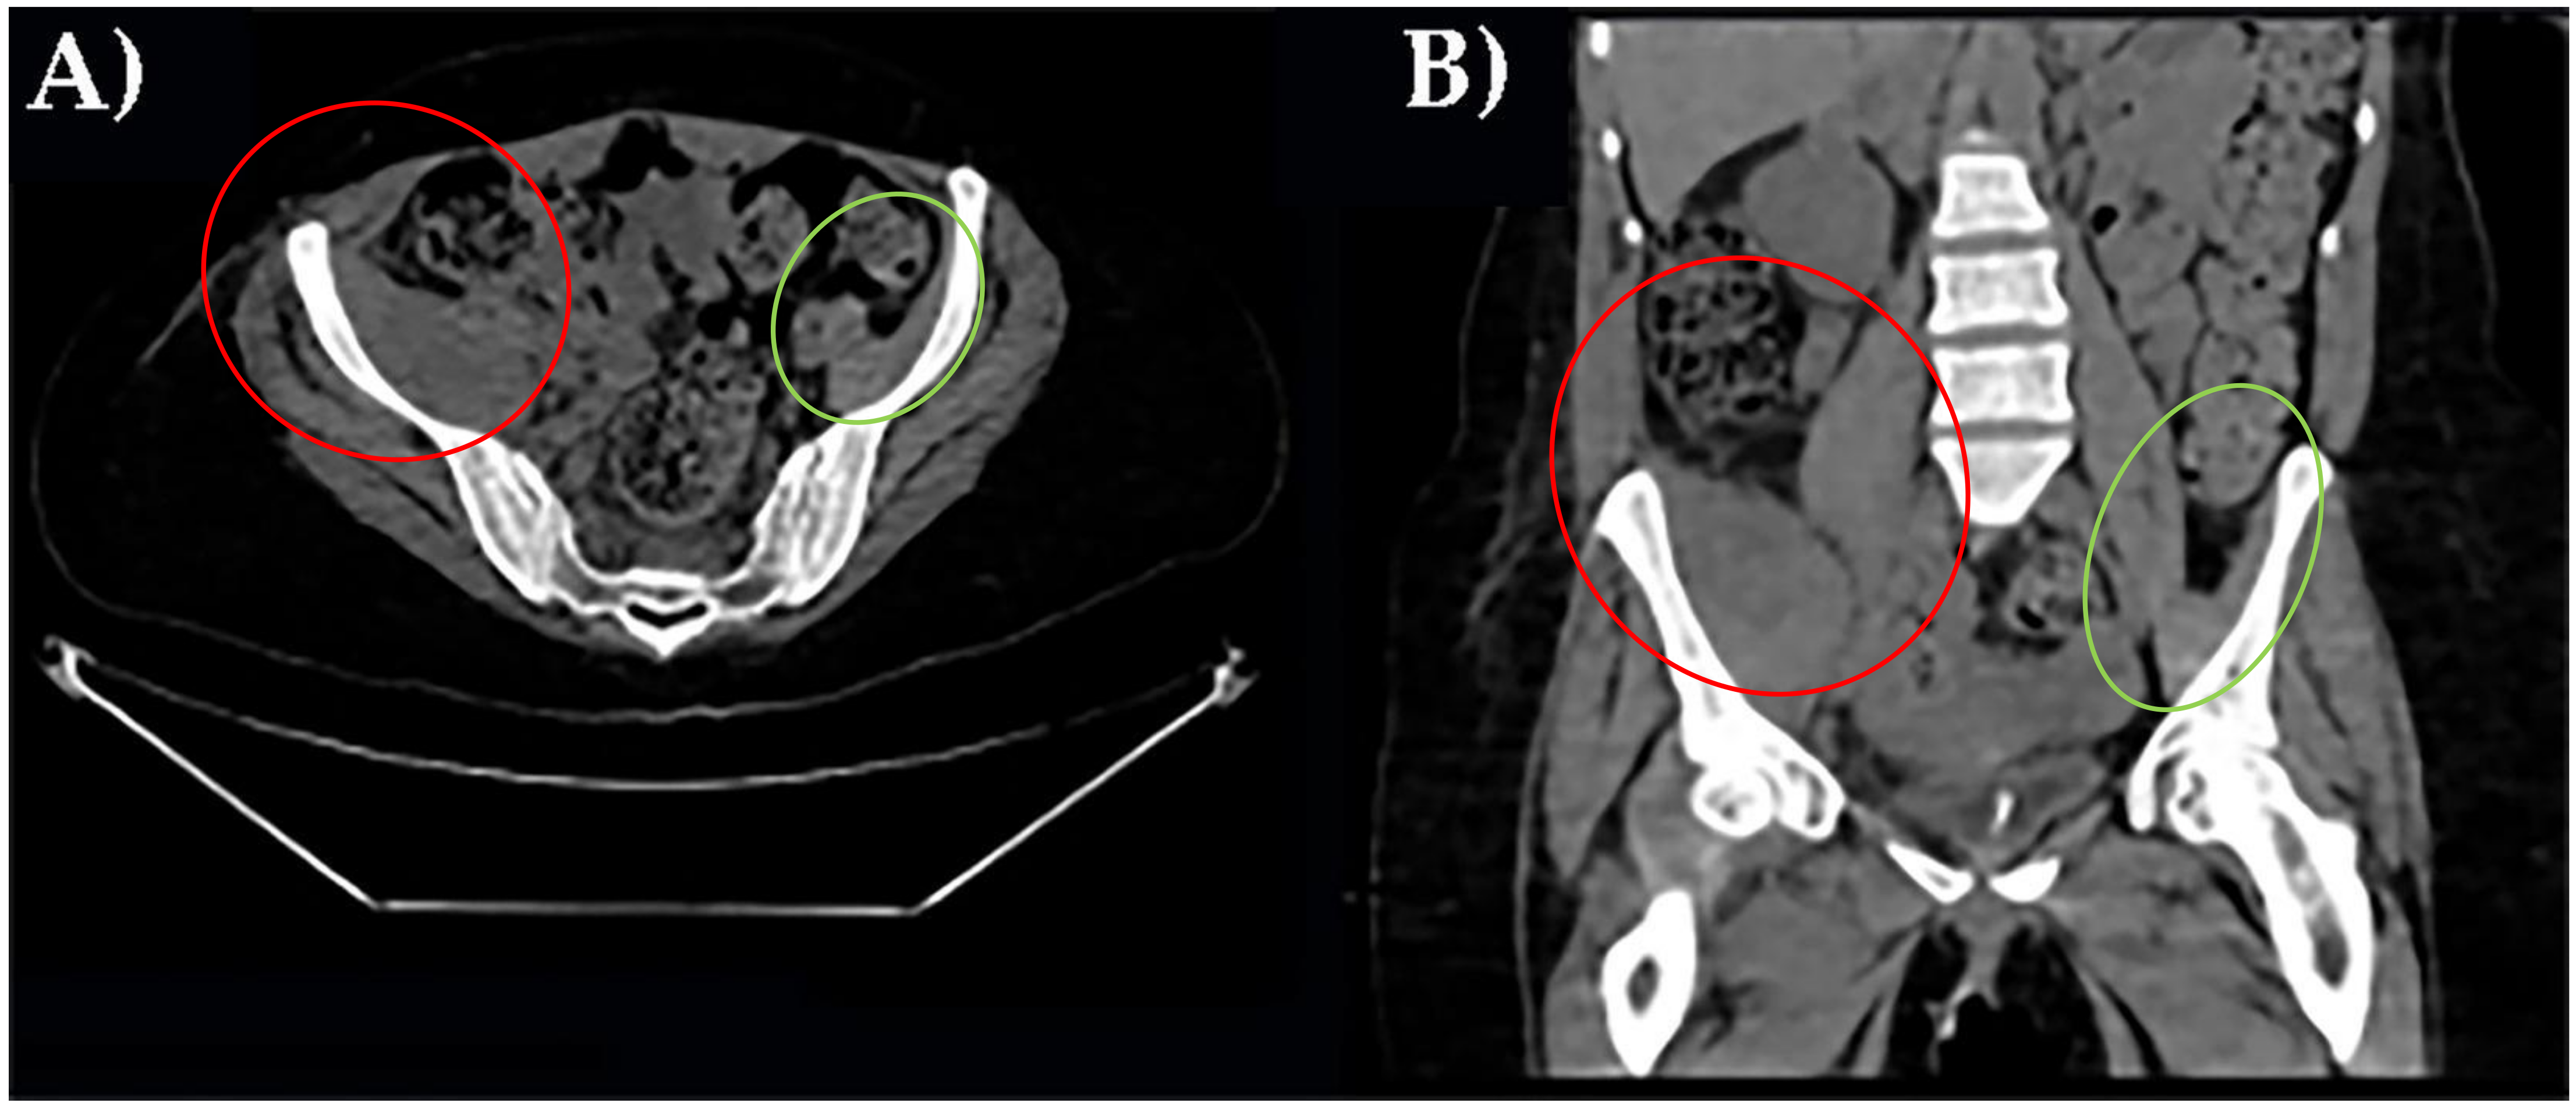

Three different instrumental imaging examinations were performed. An ultrasound study excluded a peritoneal effusion but was not more informative for extensive meteorism. CT without contrast revealed an enlargement of right iliac muscle, slightly parenchymal inhomogeneity without signs of overt bleeding and excluded other causes of leg pain (Figure 1).

Figure 1. CT axial scan of the pelvis with right ileal muscle hematoma. (A). CT coronal scan of the pelvis with right ileal muscle hematoma (B). In red, pathological finding; in green, normal appearance.